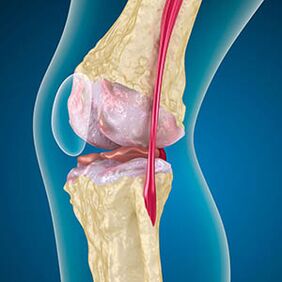

Con l'artrosi, la cartilagine che fodera i bordi delle ossa è abrasione o completamente assente. Il tessuto danneggiato non è una fonte di dolore, perché non ha recettori. L'infiammazione nelle strutture vicine provoca sintomi caratteristici.

Il corpo continua la rigenerazione dei tessuti danneggiati, ma la cartilagine cresce in modo non uniforme. Di conseguenza, si formano irregolarità che danneggiano altri elementi dell'articolazione. La natura degli osteofiti è spiegata dalla compensazione della cartilagine articolare liscia. Un'altra versione indica che la crescita di "Spurs" È associato a un tentativo di stabilizzare l'articolazione medialmente o laterale a causa dell'indebolimento muscolare.